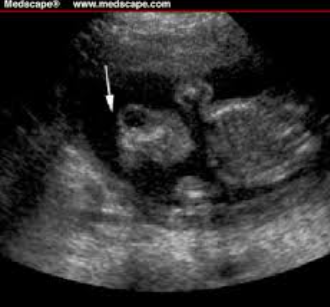

정상 태아와 비교해보면 이런식으로 차이가 나죠